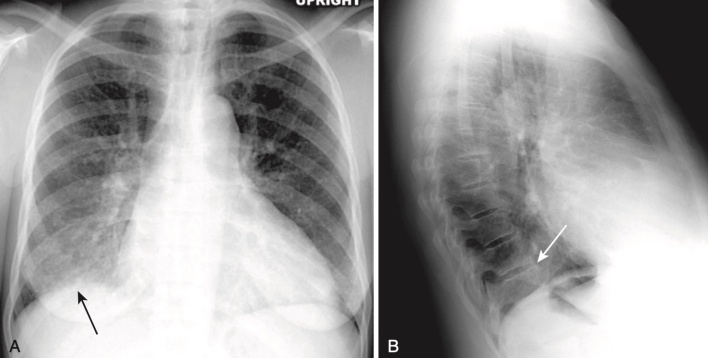

- Nguyên mẫu của viêm phổi thùy là viêm phổi do phế cầu gây ra bởi Streptococcus pneumoniae (Hình 3).

- Mặc dù chúng ta gọi nó là viêm phổi thùy, nhưng bệnh nhân có thể có các triệu chứng trước khi bệnh ảnh hưởng đến toàn bộ thùy phổi. Ở dạng cổ điển nhất, bệnh lấp đầy gần hết hoặc toàn bộ một thùy phổi.

- Bởi vì các thùy bị được nối với nhau với một rãnh liên thùy, bờ của viêm phổi thùy có thể nổi rõ rệt.

- Ở vùng các thuỳ không gắn với một rãnh liên thuỳ, bờ sẽ không rõ ràng và không đều.

- Viêm phổi thuỳ hầu như luôn luôn tạo dấu hiệu bóng bờ (silhouette sign) khi chúng tiếp xúc với tim, động mạch chủ hoặc cơ hoành, và chúng hầu như luôn chứa các phế khí đồ (hình ảnh phế quản chứa khí) nếu chúng ảnh hưởng đến các phần trung tâm của phổi.